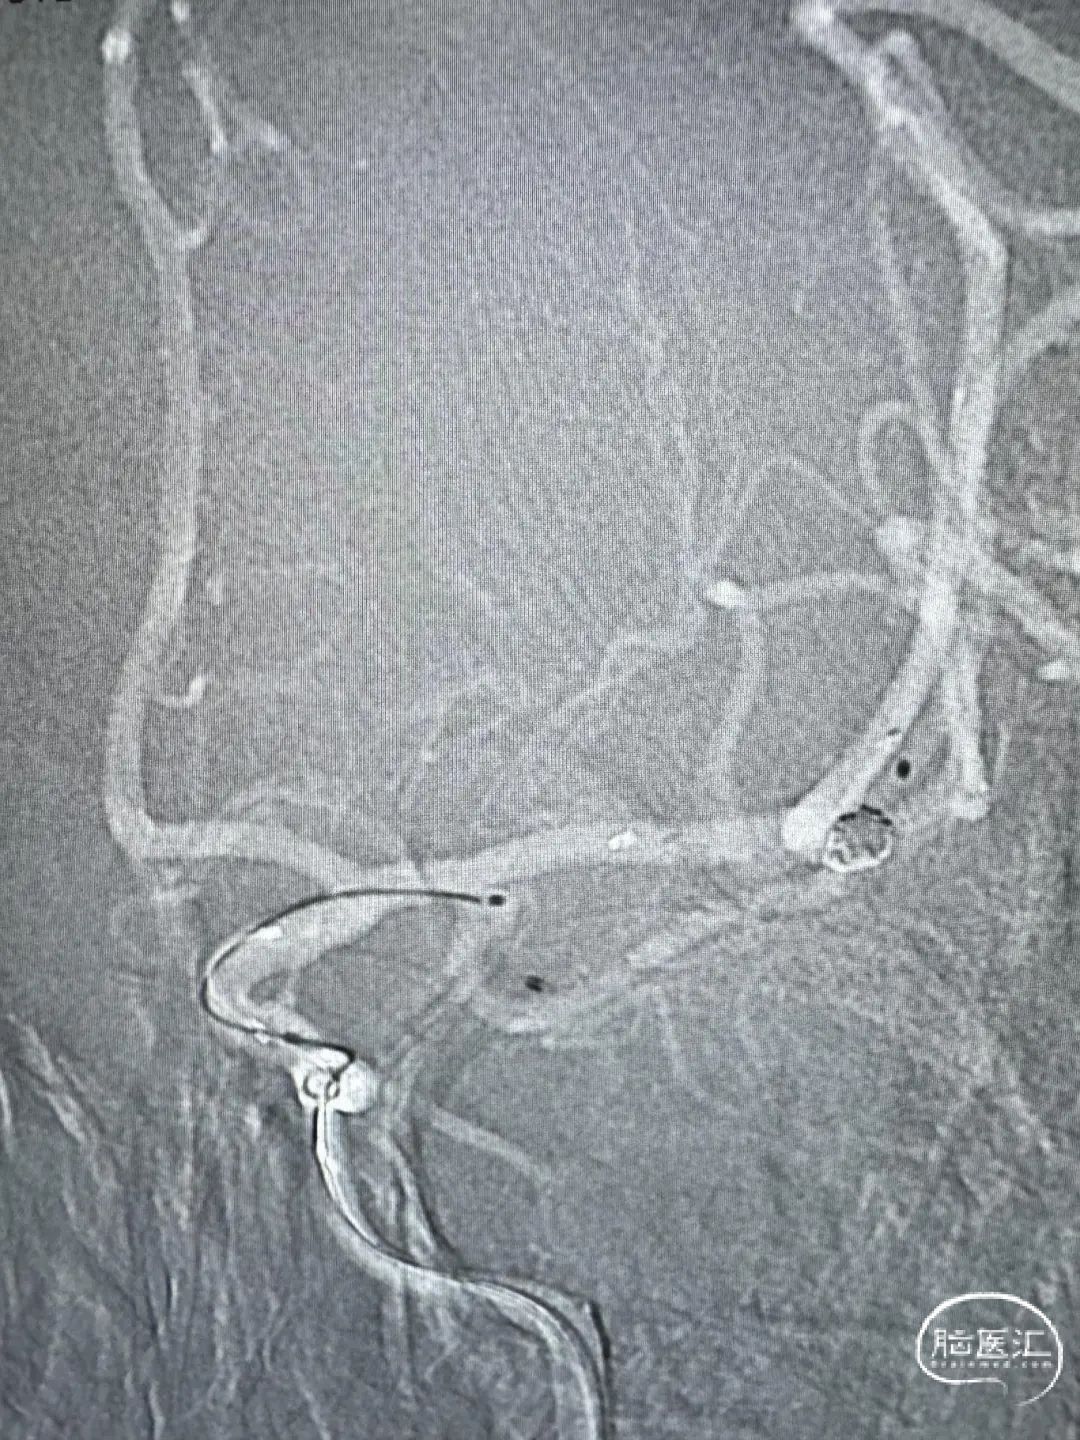

术后正侧位造影。

动脉瘤完美栓塞,一个支架,两根微导管,一根微导丝主导全程,填塞致密。